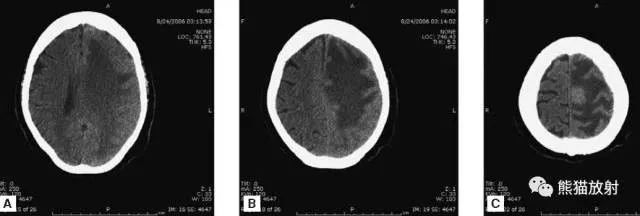

颅脑CT常用的三个窗(图A-C):图A:骨窗(the bone window)。

图B:脑窗(the brain window)。

图C:血窗(the blood window)。

图A:骨窗;主要用于明确骨折、窦腔病变、颅内积气。

图B:脑窗;可清晰显示灰白质,可发现中风的早期征象或其他导致脑水肿等表现的病变。

图C:血窗;更利于显示硬膜下或颅内出血。本例表现:骨窗示:右顶骨骨折;三个窗均示:软组织水肿并皮下积气;血窗:少量硬膜下血肿。